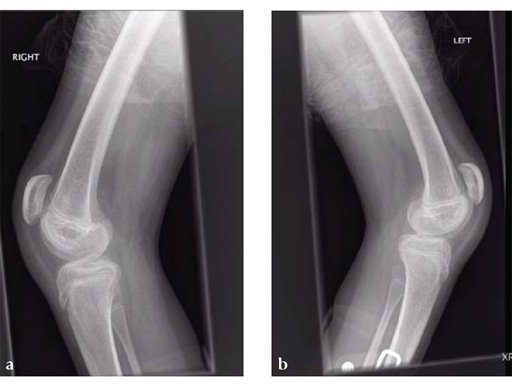

A 12-year-old girl presented for the first time to the cerebral palsy clinic. Although weak as well as spastic she was able to stand and step and wished to walk better. Physical examination revealed fixed flexion deformity of both knees. Distal femoral osteotomy with some shortening was the preferred option as hamstring lengthening and posterior knee capsule release would have caused further weakening.

Osteotomies were stabilized with the 5.0 mm LCP pediatric condylar plate. Postoperative management was non-weight bearing in splints, followed by weight bearing and rehabilitation at 6 weeks. Osteotomies healed uneventfully.